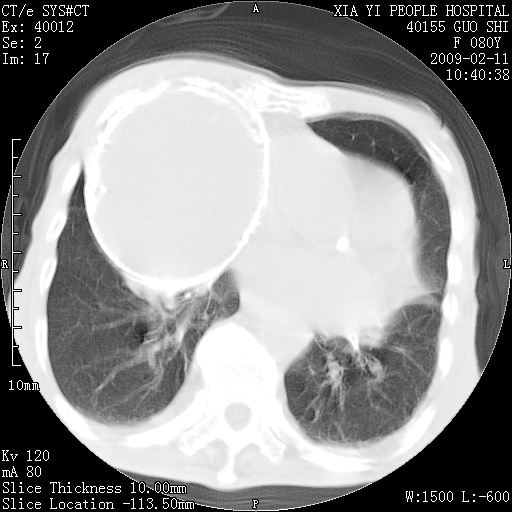

以下是引用随光逐影在2009-2-16 16:34:00的发言:[br]1)考虑右前纵隔皮样囊肿。2)双侧少量胸腔积液。

以下是引用zjzjr在2009-2-16 17:30:00的发言:[br]支持囊性畸胎瘤 双侧少量胸腔积液。